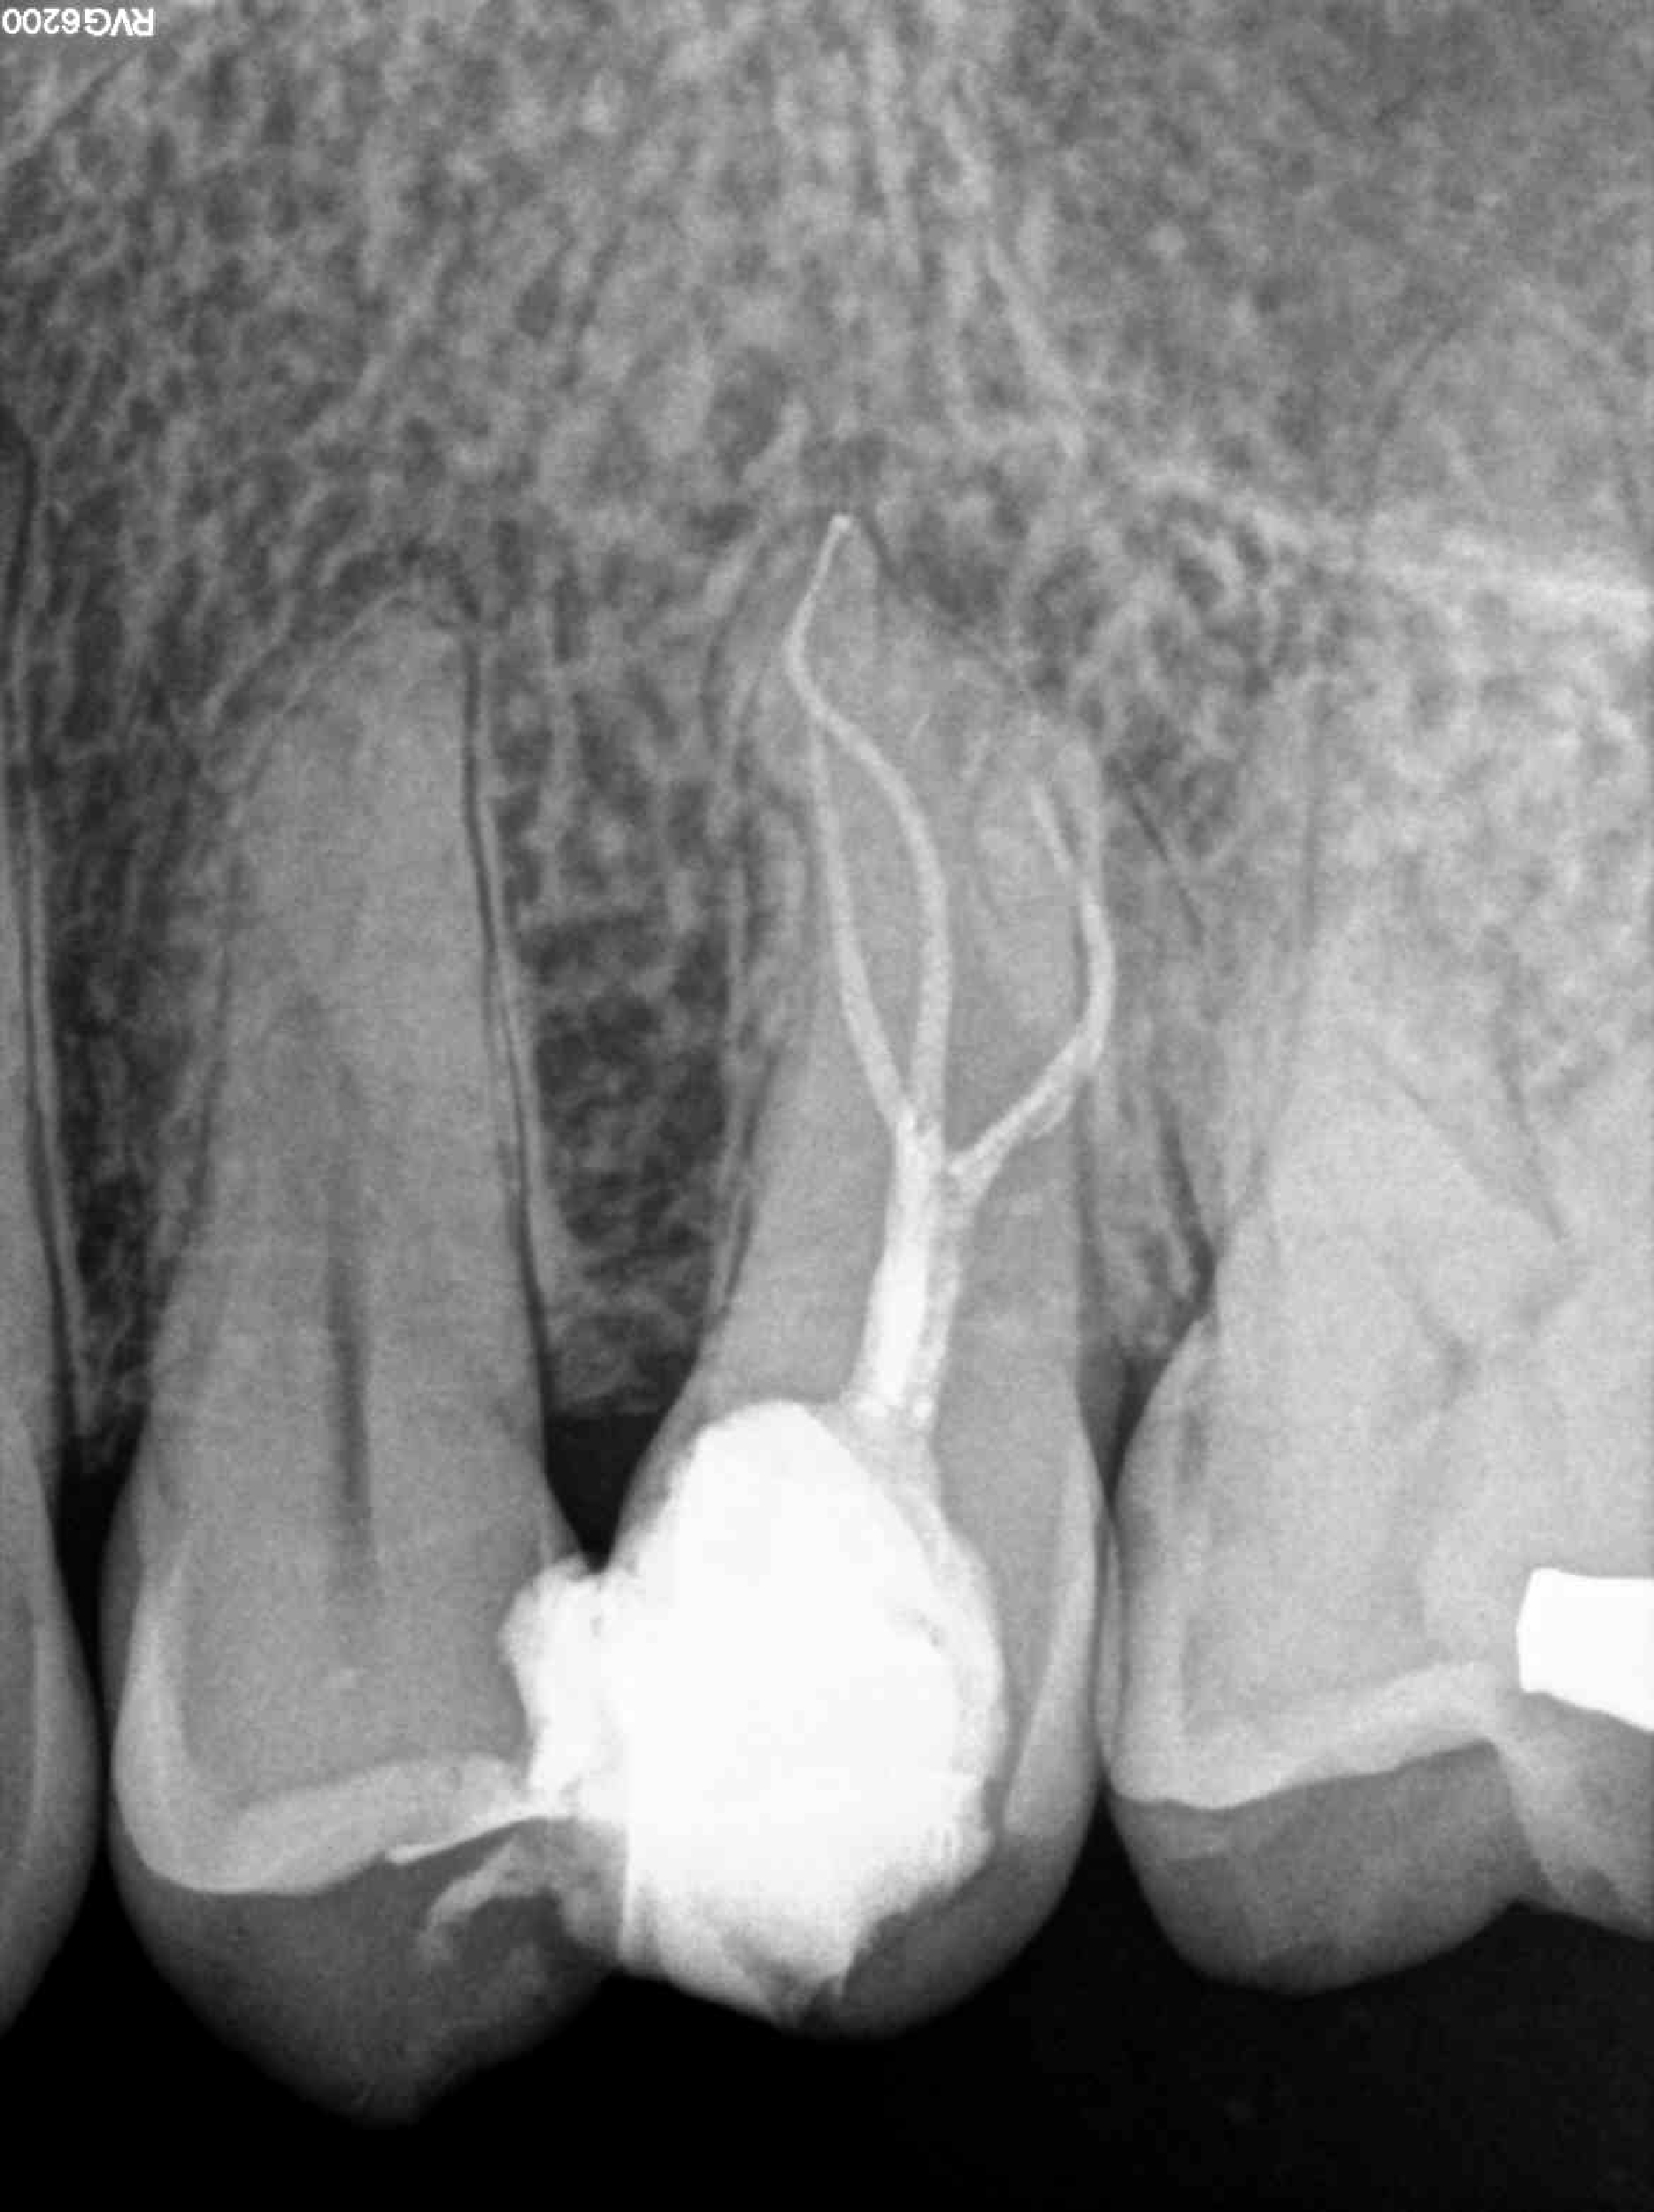

* Haz click sobre las radiografías para verlas a mayor tamaño

Haz click sobre las radiografías para verlas a mayor tamaño